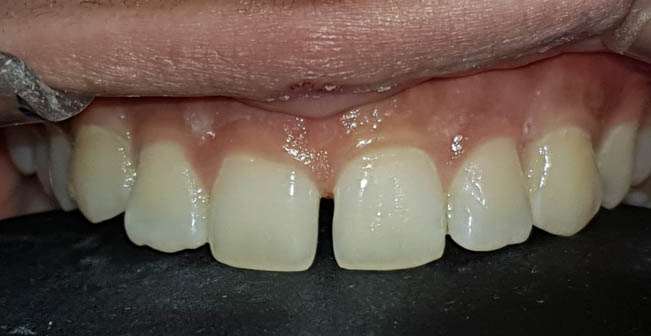

याशिवाय आजकालची प्रमुख समस्या म्हणजे पुढे आलेले दात किंवा दात वाकडेतिकडे असणे, दातांमध्ये फटी असणे की ज्यामुळे तुमचा चेहरा, तुमचं हसणं विद्रूप तर दिसतंच पण त्यामुळे खाताना, गिळताना, बोलतानाही त्रास होतो तो वेगळाच ... यावर दंततव्यगोपचार (ऑर्थोडोंटिक) हे प्रभावी माध्यम (उपचार) आहे. दाताना क्लिप्स लावून असे वाकडे तिकडे दात सरळ रेषेत येतात, पुढे आलेले दात मागे नेता येतात, दातातील फटीही बंद करता येतात. याशिवाय, जास्त वाढलेला जबड्यांची दुरुस्तीही योग्य तऱ्हेने करता येते. वाढीचे वय संपून गेल्यानंतरही, प्रौढांनाही कमी किंवा जास्त वाढलेल्या जबड्यावर शस्त्रक्रिया करून सुंदर चेहरा मिळविता येतो. उपचार चालू असताना अवघडल्यासारखे (awkward) वाटू नये म्हणून विशेषतः प्रौढांना, दातांच्या रंगाच्या, कमीत कमी दिसणाऱ्या क्लिप्स ही उपलब्ध आहेत. याच सोबत अलायनर्स(aligners)म्हणजे अजिबात न दिसणाऱ्या क्लिप्स सुद्धा उपलब्ध आहेत.

समोरचे दात जर किडलेले असतील तर त्यामध्ये दातांच्या रंगाचे फिलिंग (कंपोझिट) करता येते. खूपच किडलेल्या दातांना रूट कॅनाल ट्रीटमेंट करून, अगदी हुबेहूब नैसर्गिक दिसणारे सिरामिक किंवा झिरर्कॉनियम चे दातही बसविता येतात .